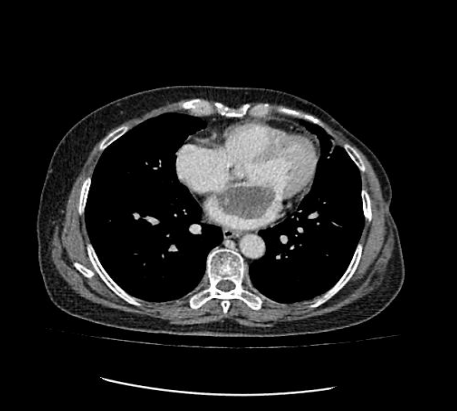

患者為一名57歲的女性,心慌、胸悶的癥狀已有一年多,一直以為是“感冒”而沒放在心上。最近經(jīng)人介紹到我院檢查,經(jīng)心臟超聲檢查發(fā)現(xiàn)左心房上長了一個雞蛋大小的黏液瘤。雖說是良性的,但生長位置在二尖瓣口,如果黏液瘤碎片或瘤體表面血栓脫落,可發(fā)生體循環(huán)或肺循環(huán)的栓塞,隨時有猝死的危險。以往此類疾病必須通過傳統(tǒng)胸部正中切口實施手術(shù),病人術(shù)后要經(jīng)過3-6個月左右的恢復(fù)期,患者創(chuàng)傷大、恢復(fù)慢、出血較多、切口瘢痕明顯、心理負(fù)擔(dān)重,無論是對身體還是心理都是一次嚴(yán)重創(chuàng)傷。為患者實施全胸腔鏡技術(shù)摘除左心房黏液瘤手術(shù),在不破壞患者破壞胸骨穩(wěn)定性的前提下,只需在患者胸壁上開2個“鑰匙孔”樣大小觀察孔和1個4cm的操作孔即可進(jìn)行手術(shù),最大限度減少術(shù)后疼痛和創(chuàng)傷,縮短術(shù)后恢復(fù)時間。